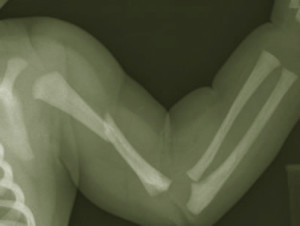

Верхние конечности страдают очень часто. К сожалению, это порой выражается в переломах, то есть нарушении целостности кости. Одним из видов таких повреждения являются переломы плеча. Это очень распространенная травма, получить которую довольно легко. Стоит неудачно упасть на плечо, особенно если слабые кости, как сразу же повредится плечевая кость. Такая травма не часто бывает очень серьезной, но такие случаи все же есть. В любом случае, необходимо вовремя обнаружить перелом и начать оказывать первую помощь.

Понять, произошел ли перелом, несложно. Обычно такая травма сопровождается характерным переломом, а также сильной болью. В области повреждения образуется отек. Пострадавший человек не может двигать рукой, так как даже малейшая попытка сделать движение сопровождается болью. Если произошел перелом со смещением, наблюдается деформация в месте травмы. Если произошел открытый перелом, могут торчать костные отломки, а сама рана может сильно кровоточить. От вида перелома зависят действия при первой помощи. Для начала стоит рассмотреть, как действовать, если произошел закрытый перелом.